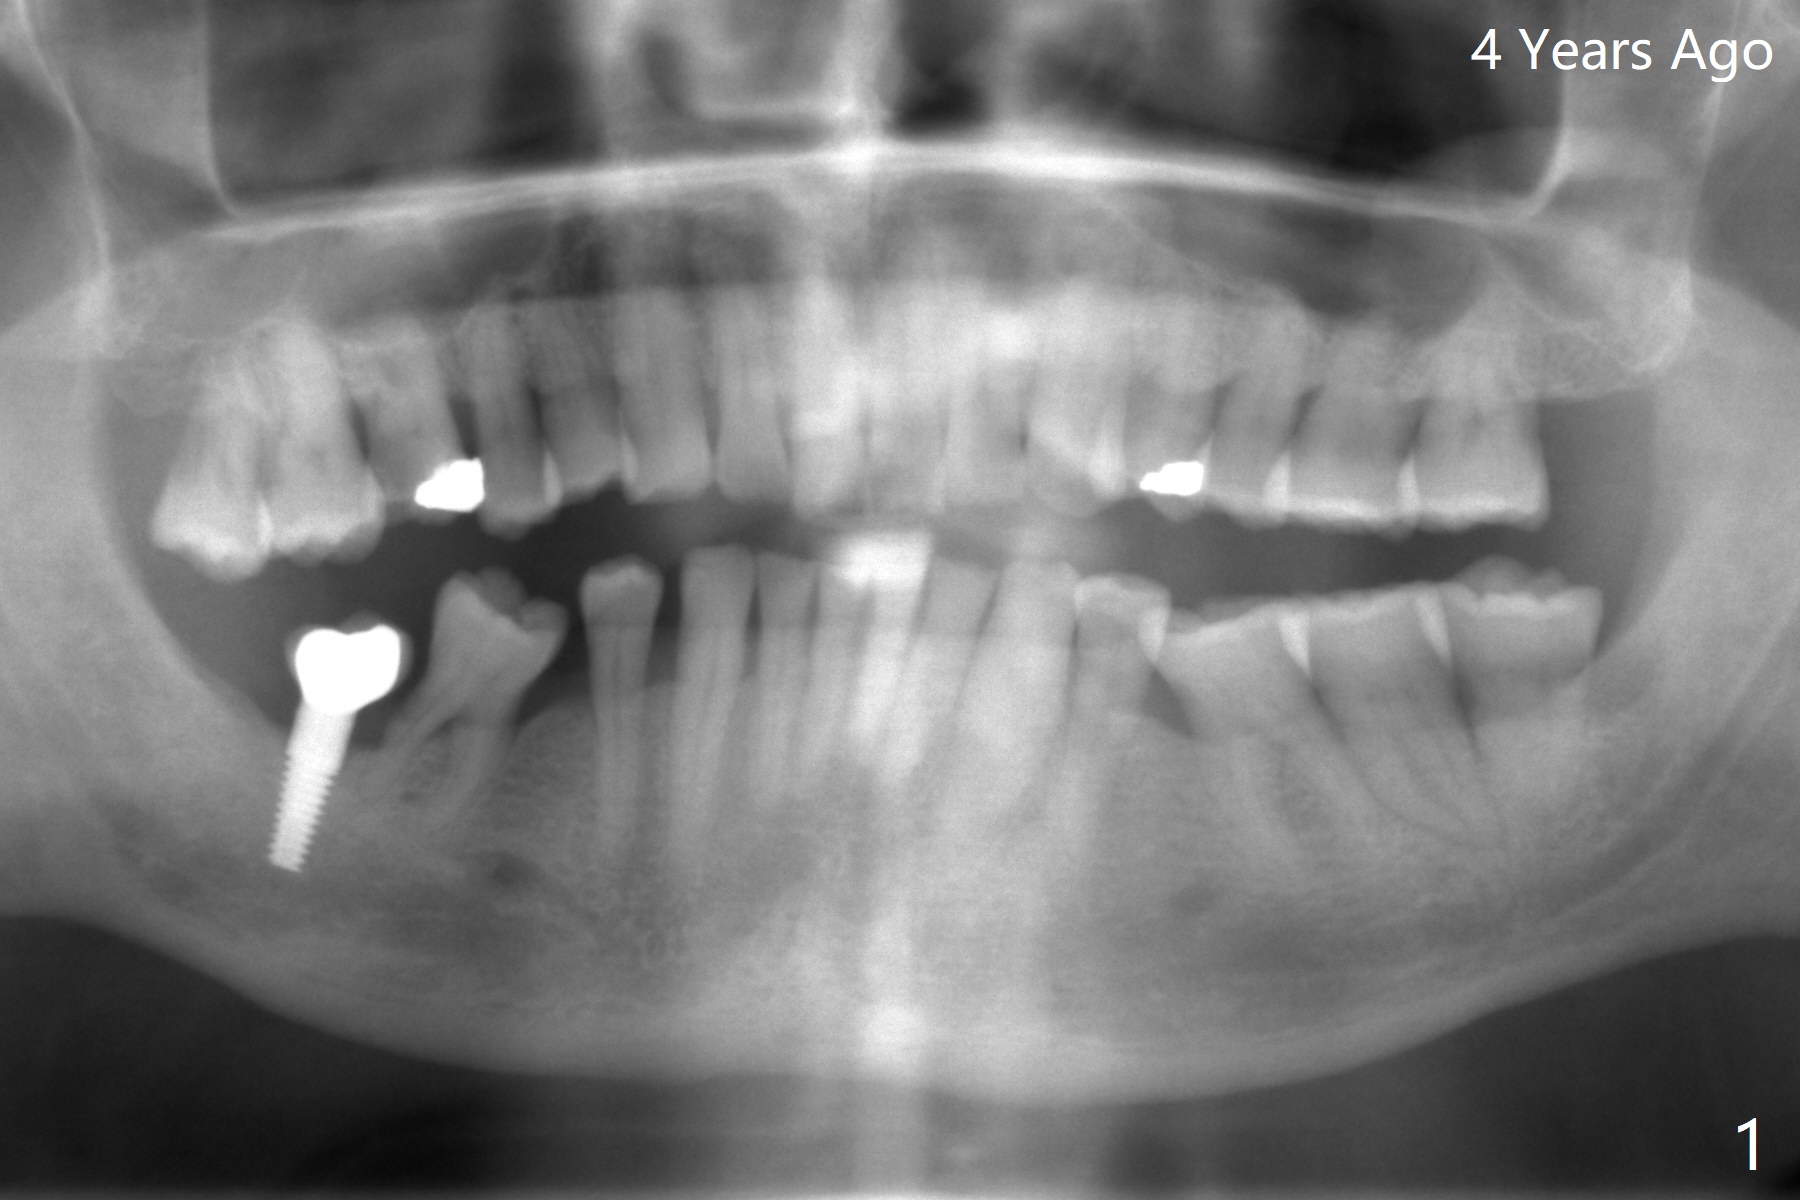

64岁男4年前完成右下7种植,局部矫正病人半途而退(图一),最近6不能保留,准备拔除6;5,6种植。为了减少射线干扰,在3,4(no bonding),7咬合面放置树脂标记(图二:*),先拍摄CT(图三),然后取模或者口腔扫描,DICOM, STL文件/图像就可以融合,制作准确导板(图四)。5,6金属圈不在一个平面,前者有利于钻洞准确,后者有利于钻头进入,常用于第二磨牙,张口度有限时。